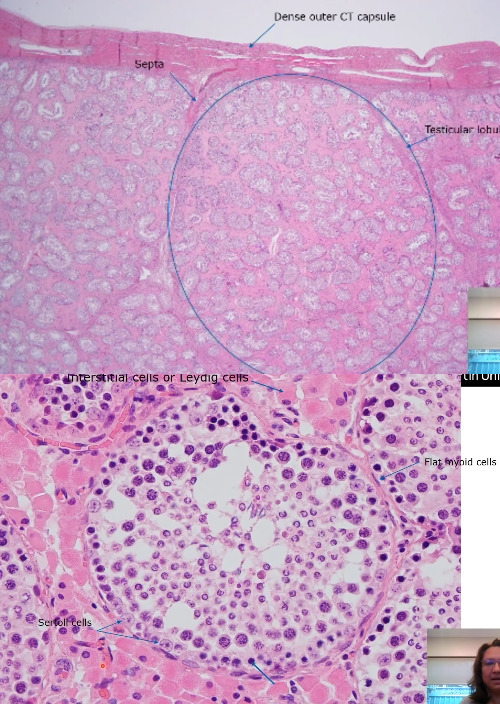

Testes

A

Dense CT capsule (tunica albigunea)

Extends into the testes as septa

Seminiferous tubules

Surrounding seminiferous tubules are Leydig cells

Mucosa of seminiferous tubules made up of Sertoli cells

Flat cells on outside of seminiferous tubules are Myoid cell (smooth muscle cells)

CT framework throughout